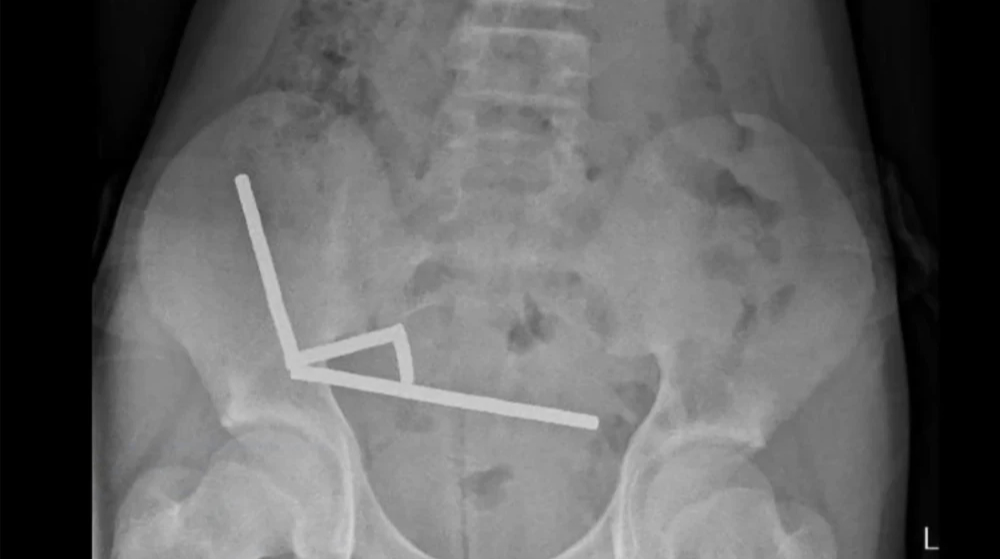

Photo: New Zealand Medical Journal

An X-ray showed that inside the child’s intestines foreign objects were lined up in four straight lines.

“They were in separate parts of the intestine, held together by magnetic force”the doctors added.